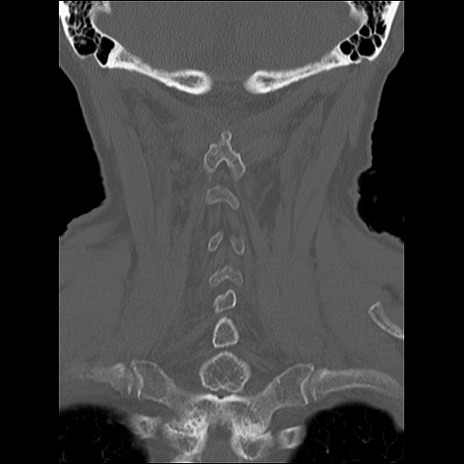

症例48 頚椎CT(冠状断像)

頚椎CT